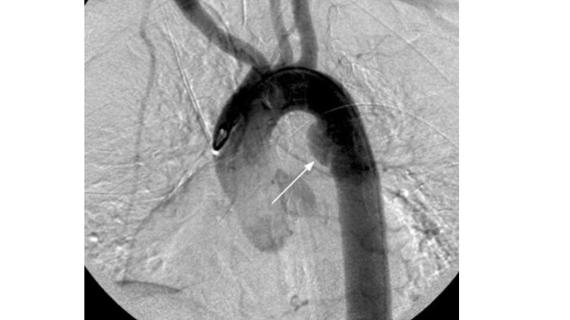

Стеноз сонной артерии при атеросклерозе возникает вследствие нарушения микроциркуляции по причине отложения жировых скоплений в артериальной стенке. Сонная артерия обеспечивает кровоснабжение значительной части...